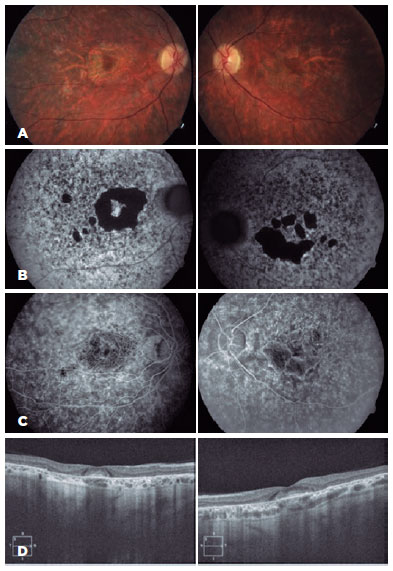

Her visual acuity (BCVA) was 20/20 in the right eye and 16/20 in the left eye. Anterior biomicroscopy and intraocular pressure findings were normal. Fundus examination showed advanced perifoveal RPE and choriocapillary atrophy, with central foveolar respect, symmetrically in both the eyes in addition to the pigmentary accumulations in the peripheral retina without optic nerve pallor, bone spicules, or attenuated vessels (Figure 2). FA and fluorescein angiography autofluorescence (FFA) were performed, with central hypoautofluorescence confirming the symmetrical absence of RPE and choriocapillaris and an annular hyperfluorescent bull’s-like perifoveal ring without the “dark choroid” sign characteristic of Stargardt disease. Spectral-domain optical coherence tomography (SD-OCT) showed moderate retinochoroidal atrophy with central subfoveal accumulation in both eyes (Figure 3).

Case 1’mother (an 82-year-old woman) was also examined at the same visit (Case 2). She reported progressive visual acuity loss, which was more pronounced in recent years. Her BCVA was 10/20 in both the eyes and fundus examination revealed extensive atrophy of the RPE and choriocapillaris in perifoveal patches with central respect, predominantly in the posterior pole and the equator region (Figure 3).

FFA and FA findings were identical to those of her daughter, with a greater degree of progression, consisting of external retinal and choriocapillary atrophy and preserved Haller’s layer. SD-OCT showed atrophy and subfoveal accumulation associated with an epiretinal membrane (Figure 3).